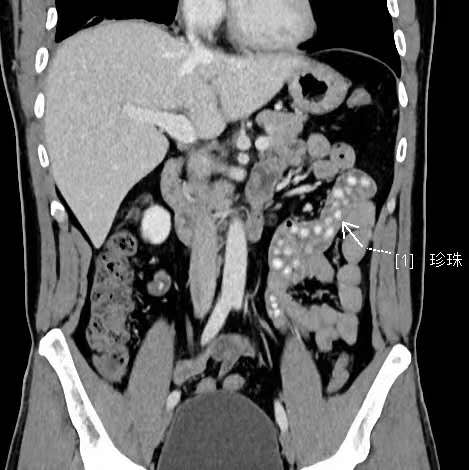

拍出來的片子讓醫(yī)生大吃一驚,小林的胃腸道里布滿了高密度陰影。仔細(xì)一看,醫(yī)生發(fā)現(xiàn)是一顆顆沒有消化的東西,像珍珠奶茶里面的“珍珠”。

“密密麻麻,粗略估計(jì)有幾十顆。”影像科副主任醫(yī)師薛貞龍告訴現(xiàn)代快報(bào)記者,奶茶里的珍珠很難消化,CT顯示腸腔內(nèi)圓形結(jié)節(jié)狀高度密影。他提醒,對于炎性腸病患者,尤其是伴有輕中度腸道狹窄的患者,最好別喝奶茶,很容易誘發(fā)腸梗阻。